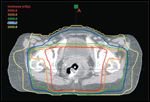

FIGURE 1

Radiation Fields and Doses

Tempering these positive results is the high rate of treatment-related morbidity associated with chemoradiation for anal cancer (Table 1). The acute toxicity induced by these treatments can be severe. In the recent Radiation Therapy Oncology Group (RTOG) 98-11 trial, in which conventional radiation therapy techniques were employed (Figure 1), 87% of patients experienced grade 3/4 acute toxicity. Patients who received 5-FU/mitomycin with radiation therapy as part of this trial experienced Common Toxicity Criteria for Adverse Events (CTCAE) v2.0 grade 3/4 skin and gastrointestinal toxicity rates of 48% and 35%, respectively.[12] Similarly, preliminary results of a United Kingdom Coordinating Committee on Cancer Research (UKCCCR) study comparing 5-FU/mitomycin–based chemoradiotherapy to a cisplatin/5-FU–based chemoradiotherapy regimen reported a 61% grade 3/4 nonhematologic toxicity rate in the mitomycin arm.[13] Treatment breaks induced by or used to mitigate these high treatment-associated toxicity rates are common and likely compromise therapeutic efficacy (discussed below).